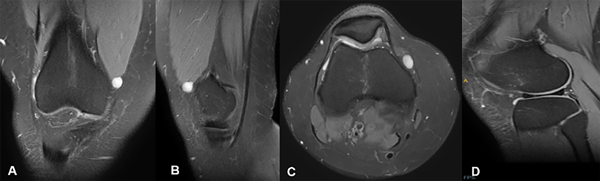

Trae el resultado de una ecografía con impresión diagnóstica de ganglión. Solicitamos una RM donde se evidencia e informan una estructura ovoidea de señal quística, superficial al retináculo medial en su tercio proximal, de 10 × 8 × 8 mm y lesión en el menisco externo, en cuerno medio y posterior (fig. 1).

Figura 1: RM de rodilla derecha. A) Corte coronal. B) Corte sagital. C) Corte axial. Imagen de aspecto quístico en relación con el retináculo medial. D). Corte sagital. Lesión radial del menisco externo en la unión del tercio medio y anterior.